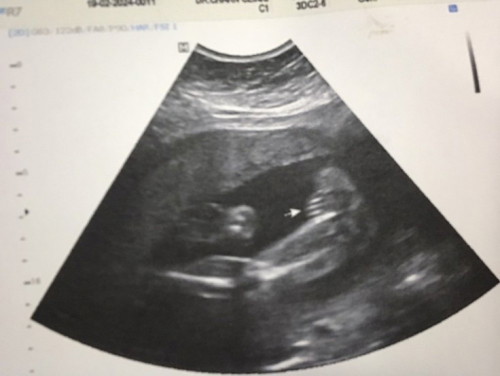

คือแม่บ้านนี้แอบไปซาวด์เพศลูกที่คลีนิคมา หมอบอกน้องเป็นผู้หญิง เลยอยากเห็นรูปซาวด์ของแม่ๆบ้านอื่นว่าเป็นเหมือนกันไหมค่ะ แม่อยากมั่นใจ555 #ขอบคุณล่วงหน้าสำหรับความคิดเห็นค่ะ

บ้านนี้หมอที่ รพ บอกผู้หญิง แม่ไปซาวด์ที่คลินิกหมอก็บอกผู้หญิง ส่วนตัวแม่อยากได้ผู้หญิงอยู่แล้ว แต่แม่ก็ยังไม่มันใจค่ะ ทีม มิถุนายน จร้า

หมอบอกได้ลูกสาว 99% คะ แต่อิแม่อยากได้ ผู้ชายยยย

แม่บ้านนี้ คุณหมอคอนเฟิร์มว่าได้ลูกสาวค่ะ🥰

บ้านนี้หมอบอกว่าผู้หญิงค่ะ ทีมมิถุนายน67